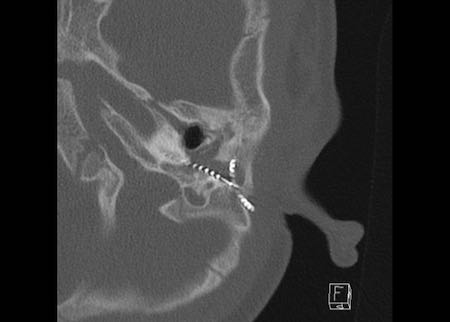

Hình ảnh

Bé trai 8 tuổi được cấy ghép ốc tai hai bên. Vị trí bình thường ở tai phải.

Một điện cực được đặt đúng vị trí với tất cả các kênh của nó, hiện ra như một chuỗi hạt, nằm trong ốc tai và xoắn lên theo hướng đỉnh ốc tai.

Tiếp tục xem hình ảnh của tai trái.